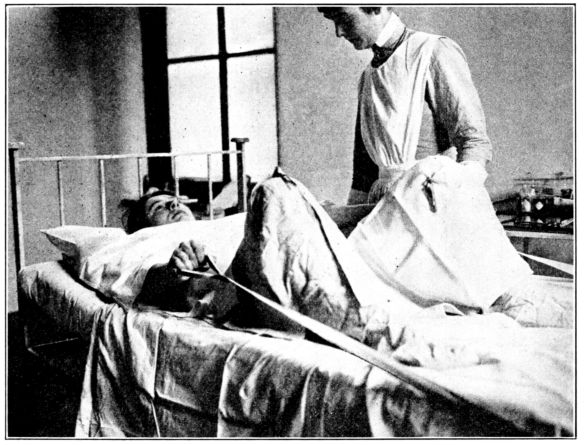

| 83. | Patient pulling on straps while bearing down during second stage | 264 |